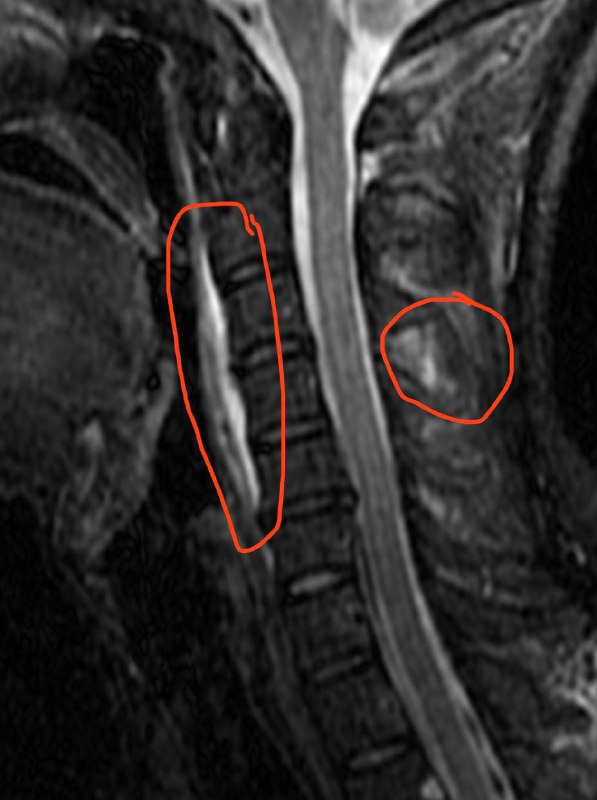

Пациент 35 лет. Жалобы на онемение правой руки. Других жалоб нет.

Кроме того, следует предположить неполное повреждение межостистой связки C4-C5

Первый тип перелома зуба C2 и перелом боковой массы атланта справа. Тактика - консервативная.

Характер травмы:

Упал с велосипеда головой вниз.